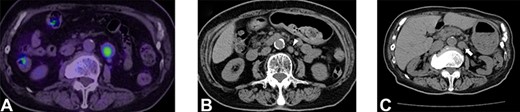

An 80-year-old woman underwent distal pancreatectomy with lymphadenectomy for PNEN. The pathological findings were as follows: well-differentiated NEN, tumor size of 80 mm, negative resection margins, negative lymphovascular invasion, no lymph node metastases and a Ki-67 index <1%. Five years after the pancreatectomy, nodal metastasis was noted near the abdominal aorta on positron emission tomography and CT (Fig. 2A). A para-aortic lymphadenectomy was performed. The pathological finding was metachronous nodal recurrence of PNEN and a Ki-67 index of 10%. Nine years after the pancreatectomy, nodal metastasis recurred near the abdominal aorta (Fig. 2B). We performed a second para-aortic lymphadenectomy, and the pathological finding was metachronous nodal recurrence of PNEN, with a Ki-67 index of 15%. Eleven years after the pancreatectomy, a third metachronous nodal recurrence appeared near the abdominal aorta (Fig. 2C). A third para-aortic lymphadenectomy was not performed because of severe aortic stenosis. Since somatostatin receptor scintigraphy revealed positive SSTR-2, 120 mg of lanreotide was administered. She complained of diarrhea as a side effect. The patient maintained stable disease for 14 years after pancreatectomy.

Selected abdominal computed tomography and positron emission tomography–computed tomography images: Case 2. (A) Recurrence for the first time: para-aortic mass measuring 24 mm with accumulation on positron emission tomography (SUVmax: 5.1). (B) Recurrence for the second time: para-aortic mass measuring 15 mm (arrowhead). (C) Recurrence for the third time: para-aortic mass measuring 24 mm (arrow).